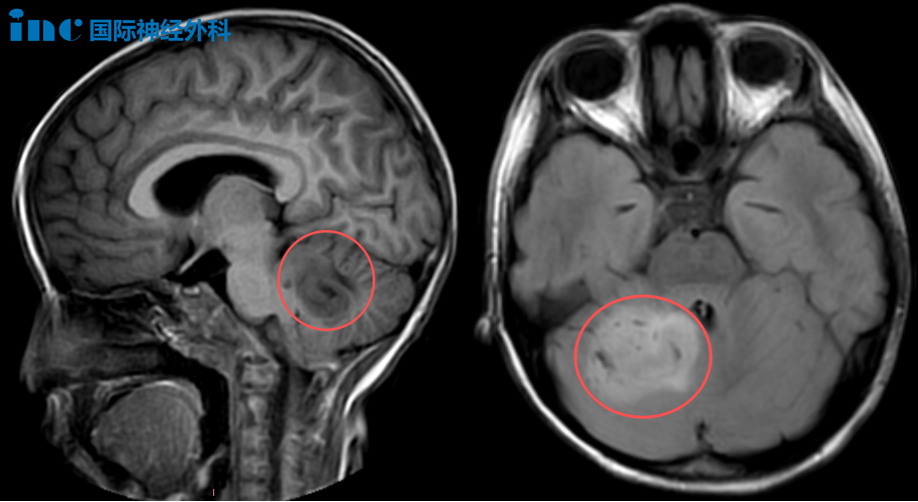

病例一:7岁女性小脑占位病变

2025年9月15日,未满7岁的女性患儿乐乐放学回家后向父母诉说自己白天出现头晕和疲乏感。检查发现"小脑占位性病变",考虑低级别胶质瘤。尽管乐乐后续状态有所改善,但由于病变体积较大,她仍不时出现头晕头痛、精神不振、嗜睡等症状。面对这一情况,父母深知必须尽快为孩子扫清前进道路上的障碍。

小脑半球作为人体运动的"精密指挥中心",负责同侧肢体的协调运作,确保每个动作精准、流畅且保持平衡。当该区域受损时,患者会出现典型同侧肢体共济失调症状——动作变得笨拙不协调,出现意向性震颤,甚至基本站立行走都摇晃不稳。此外,小脑缄默综合征(cerebellar mutism syndrome,又称后颅窝综合征)是小脑-脑干术后常见并发症之一,发生于后颅窝肿瘤(如脑干、小脑、四脑室肿瘤)切除术后患者,其特点以缄默症(无法言语)为主,故被称为"沉默的小脑"。

巴教授的评估带来了希望曙光:"从积极角度考虑,这很可能只是低级别肿瘤,甚至可能是错构瘤。两个积极迹象是:患儿尚未出现严重临床症状,且周围未见明显水肿,因此判断这不是高级别肿瘤。手术对我来说并非难事,我能完成!"